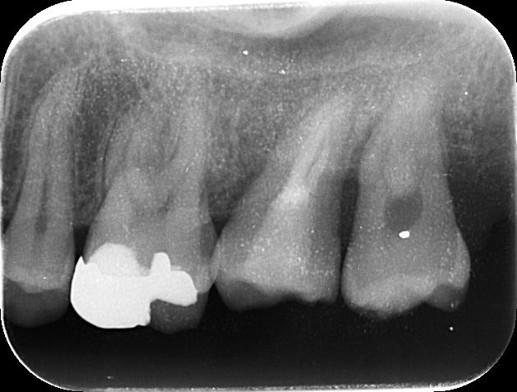

治療後

一番天然の歯に近い感覚でしっかり噛めるのがインプラントで、隣の歯に負担をかけず独立して固定します。 |

4か月 |

治療回数 |

移植した歯が周囲の骨と正常に結合せず、定着しない可能性があります。 |